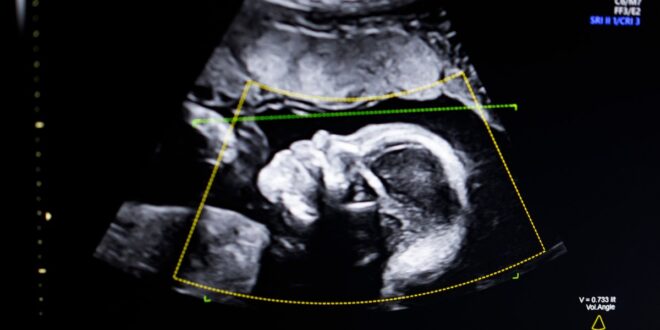

TechCrunch Disrupt Battlefield 2023 winner, Biotics AI, announced on Monday that it has received FDA clearance for its AI software that helps detect fetal abnormalities in ultrasound images.

The technology uses computer vision AI “to support fetal ultrasound quality assessment, anatomical completeness, automated reporting, and seamless integration into clinical workflows,” Bustami told TechCrunch.

Bustami said that the prenatal ultrasound has become the “cornerstone” of monitoring pregnancies, but its low-quality images can lead to misdiagnosis.